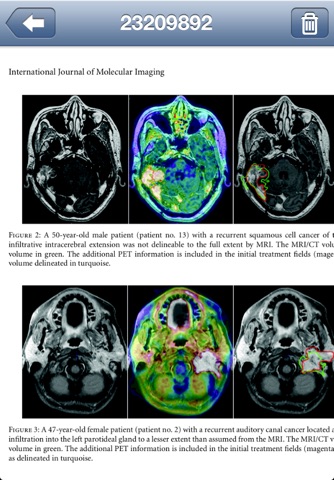

PubMed Library is designed to search and organize all your favorite articles on the go. PubMed comprises more than 19 million citations for biomedical literature from MEDLINE, life science journals, and online books that you can search from almost anywhere. Citations may include links to full-text content from PubMed Central and publisher web sites.

With PubMed Library you can make advanced searchs to PubMed, download available information of articles you are interested in, access and / or download full text of the article, download and attach a PDF file to a downloaded article, share downloaded article information by mail and many more.